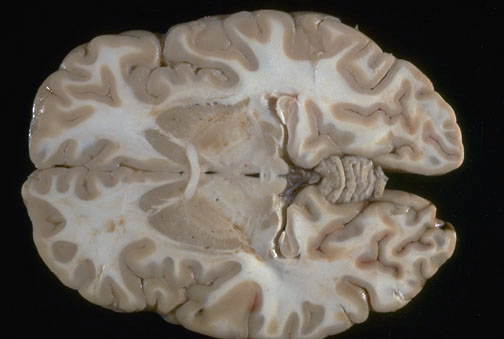

| Identify the following regions of the brain on transverse section in the image above: Anterior Commissure - Head of the Caudate Nucleus - Cerebellar Vermis - Superior Colliculi - Putamen - Hippocampus - Lateral Geniculate Nucleus - Medial Geniculate Nucleus - Globus Pallidus |